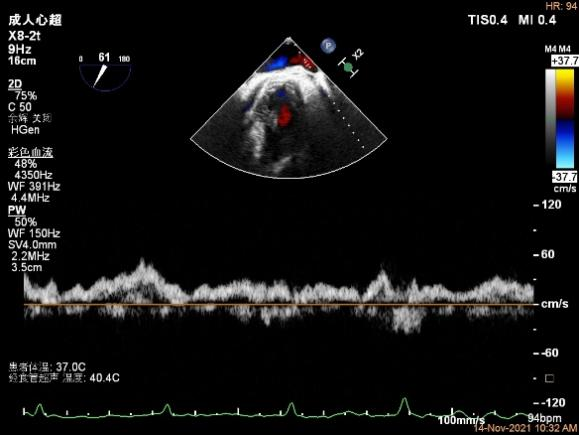

术前超声评估结果

术前超声诊断

3D-color MV view:源自于交界区的大量反流